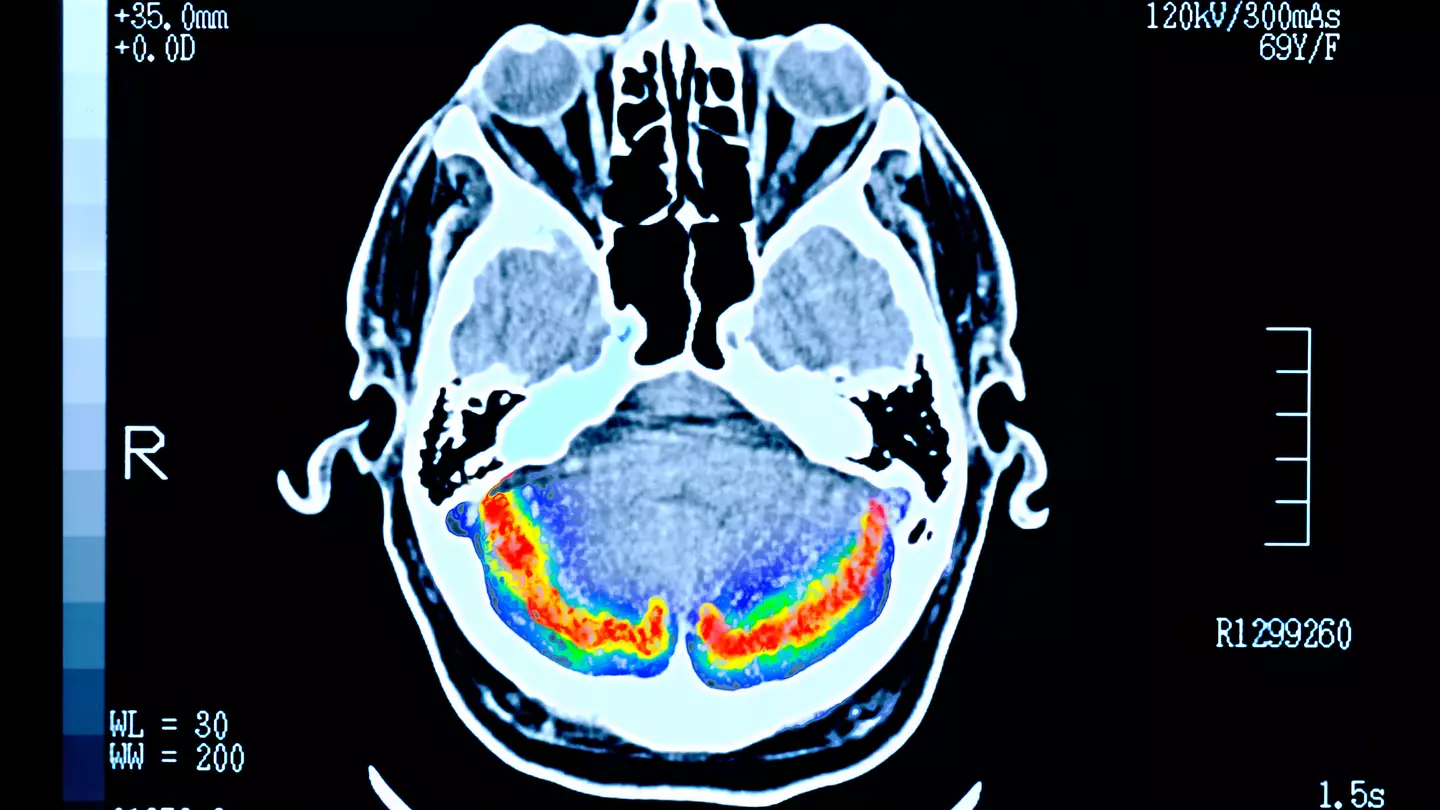

Technically, the symptoms of Alzheimer's present themselves when parts of the brain shrink (a process known as atrophy), which affects the structure and function of specific areas of the organ - as per the NHS.

And generally, it's thought that the cause of this shrinkage is a combination of age-related changes in the brain, as well as genetics, environmental and lifestyle factors.